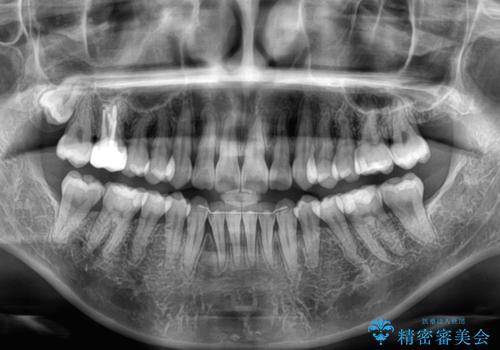

- 上下前歯のデコボコを気にして来院された患者様です。

デコボコは顕著であるものの、口元の突出感は強くないため、非抜歯にて矯正治療を行うこととしました。

元々の叢生と歯肉退縮傾向になる歯肉であったため、ブラックトライアングルが目立つことが想定されました。

治療過程でブラックトライアングル改善のため、IPR(歯と歯の間を削る)を活用しました。